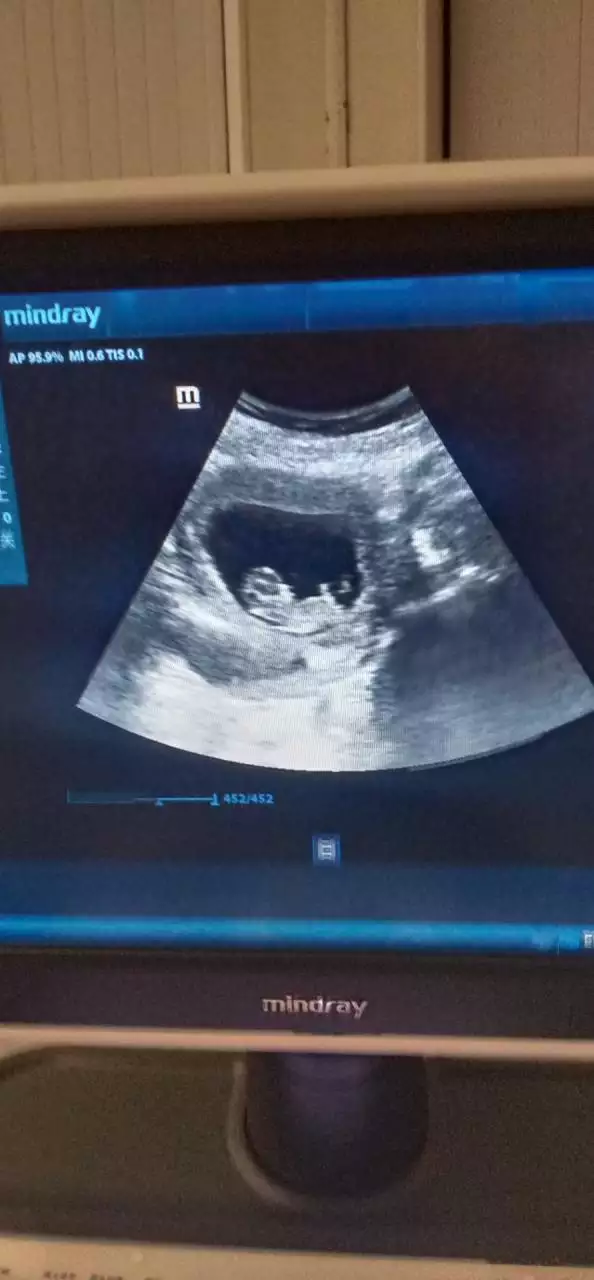

提起怀孕怎么查是女儿还是儿子,大家都知道,有人问怎样可以检测怀男孩女孩,另外,还有人想问怎么确定是儿子还是女儿?,你知道这是怎么回事?其实怀孕了差不多6个月查了是女儿,有可能是儿子吗,下面就一起来看看怎样可以检测怀男孩女孩,希望能够帮助到大家!

怀孕怎么查是女儿还是儿子

怀孕了差不多6个月查了是女儿,有可能是儿子吗

3、怀孕了差不多6个月查了是女儿,有可能是儿子吗